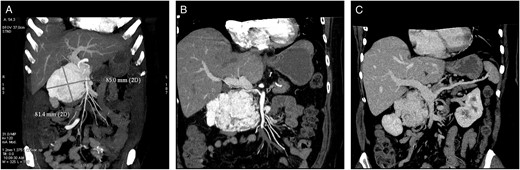

A 53-year-old, obese (body mass index 30.9 kg m−2), Caucasian woman was referred to our department with non-specific abdominal discomfort as the only presenting symptom. A large hypervascularized mass in the area of the pancreatic head was shown on abdominal ultrasonography and computed tomography (CT). There was neither lymphadenopathy nor distant spread found during pre-operative staging. Pre-operative imaging revealed an extremely hypervacularized tumour with abundant collateral vessels from the superior mesenteric artery (SMA), replaced right hepatic artery (HA), gastroduodenal artery (GDA) and right renal artery (RRA), with an early venous filling of the dilated superior mesenteric vein (SMV) and portal vein (PV) (Fig. 1A–C and Fig. 2A and B). The replaced right HA arising from SMA was crossing in between the dilated PV and overfilled tumour-draining veins (Fig. 1B). Abundant venous drainage was found. Extreme dilation of SMV and PV in both extra- and intra-hepatic course could be expected as numerous AV shunts within the tumour were present, but surprisingly, only a non-dilated, gracile splenic vein was found and no spleen enlargement was present (Fig. 1C). For better evaluation of vascular anatomy, selective digital substraction angiography (DSA) was performed. The upper portion of the tumour received main inflow via GDA and replaced right HA, the lower part via several branches of SMA (Fig. 3A and B). Capsular branch of RRA complemented tumour inflow (Fig. 3C).

(A and B) CT volume rendering images with dilated PV and an early contrast filling of dilated peritumoral veins.